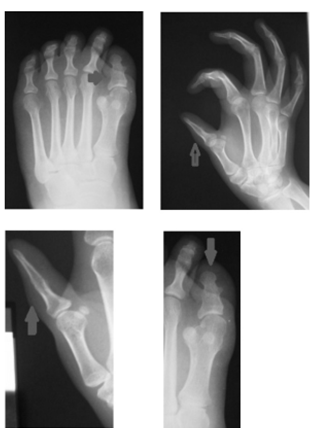

• Fibrodisplasia osificante progresiva: reporte de un caso

Carla Pérez, Mauricio Rodríguez, María Eugenia Saráchaga

60-64